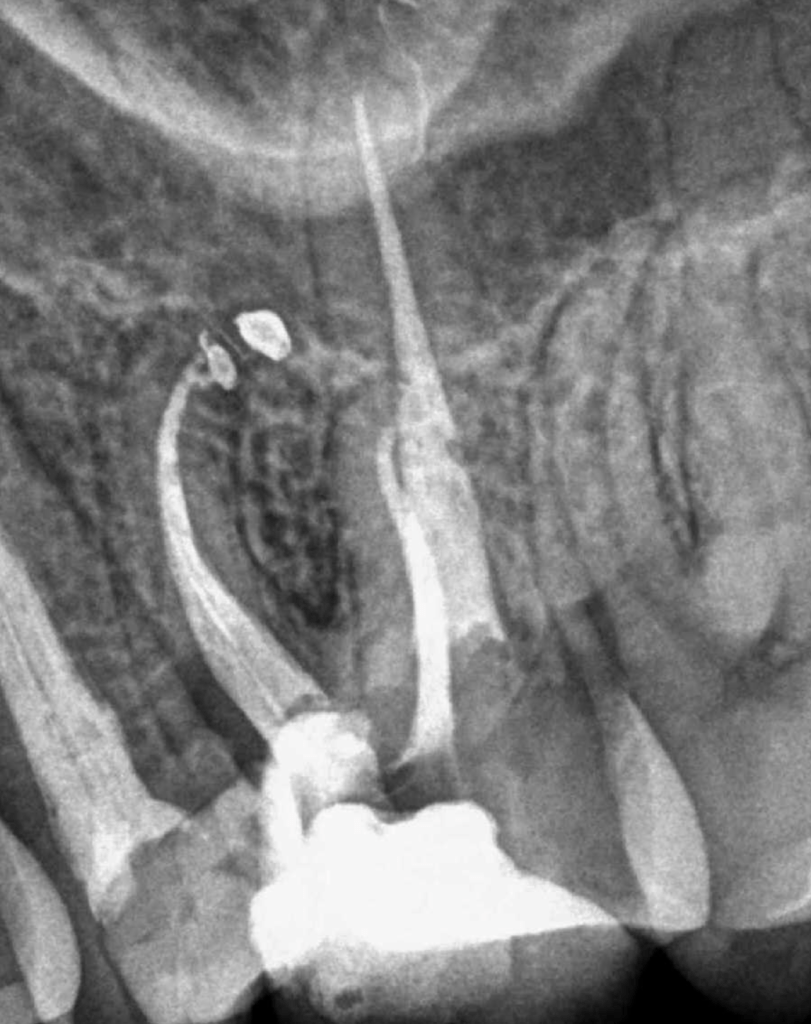

Pulpotomía biodentine + reco preendio